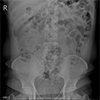

![]() |

신장요관방광 단순촬영검사 X-ray를 이용해 신장, 요관, 방광의 결석이나 구조적 이상 등을 확인합니다. |